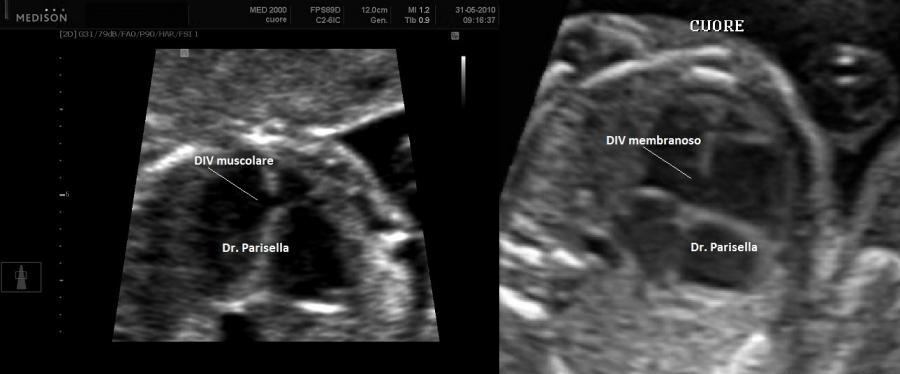

Le anomalie cardiache più frequenti sono il difetto del setto interatriale tipo ostium secondum (DIA), il difetto del setto interventricolare (DIV), anomalie della condizione cardiaca.